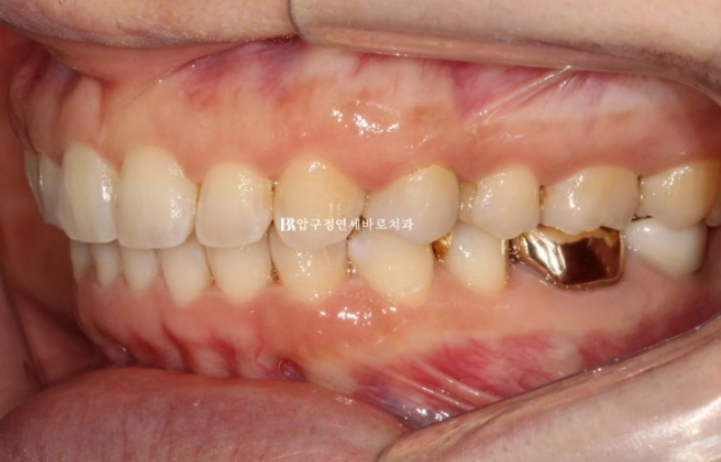

24.07

24년 2월부터 7월까지 5개월간 첫번째 세트의 장치를 다 낀 후 모습입니다.

장치 협조도가 좋아 첫세트에서 과개교합이 완전히 개선이 되었습니다.

뿐만 아니라 앞니 치축 기울어짐, 교합평면 기울어짐도 완전히 해결이 되었습니다.

임플란트가 있어 치아이동이 제한된 좌측 교합이 역시 아쉽습니다.

임플란트로 인해서 중심선을 완전히 맞출 수 없지만 좀 더 개선을 위해서 추가장치 제작에 들어갔습니다.